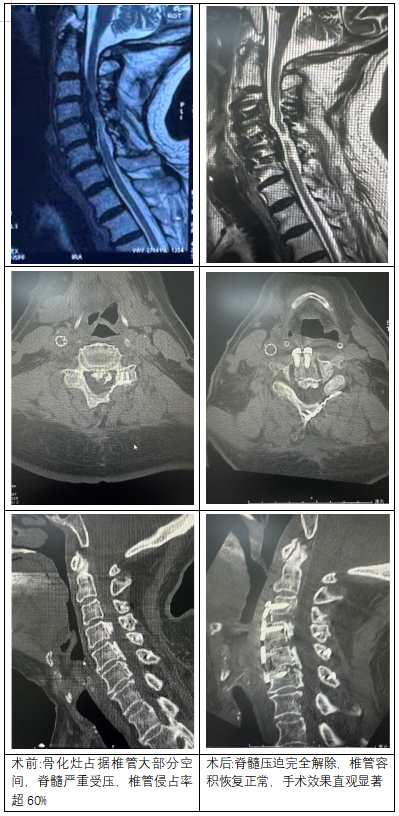

从术前术后影像对比可清晰看到,患者颈椎椎管狭窄部分被充分打开,脊髓压迫完全解除,椎管容积恢复正常,手术效果直观显著。术后患者四肢麻木无力症状即刻缓解,次日便可在支具保护下下床活动,后续恢复状况良好,生活质量得到极大改善。